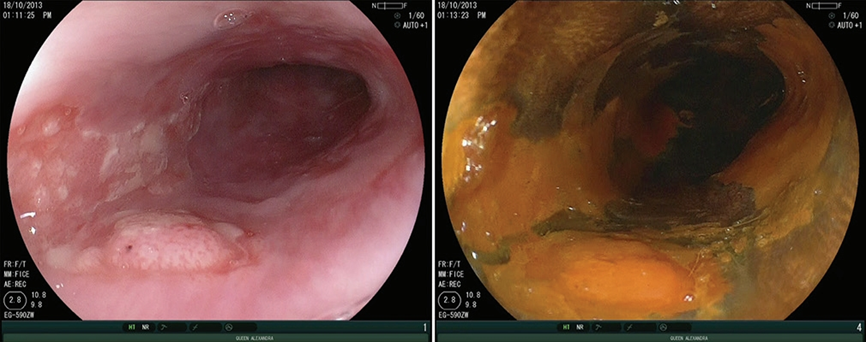

1.“粉红征”(见图1)

早期食管肿瘤区域的细胞因为缺乏糖原且病变区域鳞状上皮角质层缺失,在染色后3分钟左右出现卢戈氏液排泄区,也称为“粉红征”。

图1 (左)白光内镜下显示的0-Ia期食管鳞状细胞肿瘤病变。(右)碘染色后显示多个卢戈氏液不染区,进一步明确肿瘤区域

“粉红征”在内镜窄带成像术(Narrow Band Imaging,NBI)下观察可被强化,呈闪亮的银色,又称为“银色征”

Shimizu等人报道,当将“粉红征”用作诊断高级别上皮内鳞状细胞瘤和食管鳞癌的指标时,其敏感性和特异性分别为91.9%和94.0%。

Ishihara等人研究报道“粉红征”诊断高级别上皮内瘤或浸润性癌的敏感性和特异性分别为88%和95%。